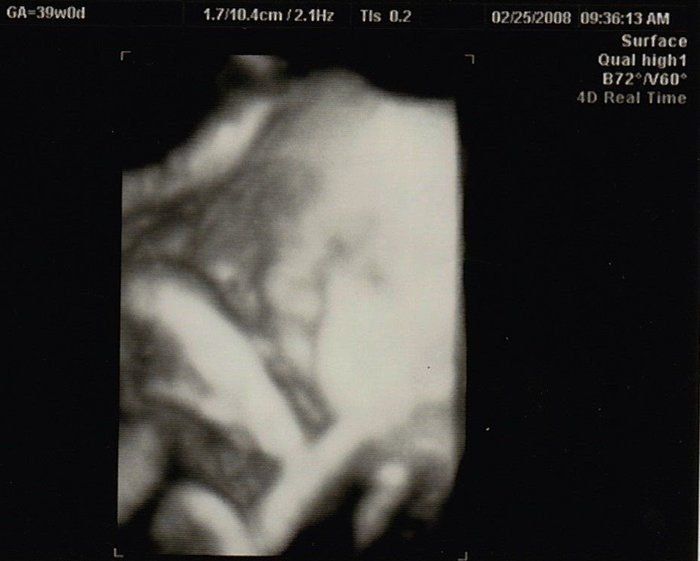

水野谷つむぎさんの妊娠39週目のエコー写真

この日が最後の検診になりました。この時点で3000gあると言われていた息子は、この2日後、ついにおなかのなかからでてきてくれました!